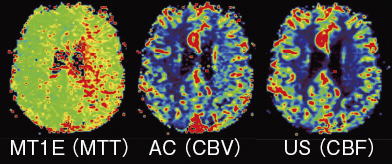

ASIST-japanでは,脳梗塞で問題となる造影剤の組織到達までの遅れ(delay)に依存しないロバストなアルゴリズムや,共通の表示方法が求められている。東芝では,解析アルゴリズムを組織TICの1次モーメントからdelayを除いた時間をMTTとし(ASIST-Japan推奨),CBVはカーブ下面積,そしてCBFはカーブの最大傾斜としている。表示方法には,推奨のカラーLUTと表示方法(WL=正常半球平均値,WW=2×WL)を採用している。

図3 カラーマップ表示例(left MCA領域慢性期脳梗塞)

(画像ご提供:宮崎大学医学部病態解析医学講座・ 小玉隆男先生)